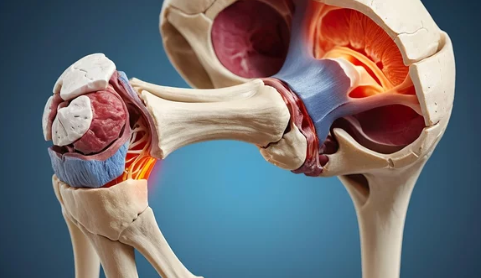

고관절 탈구는 엉덩이뼈(골반)와 허벅지뼈(대퇴골)가 연결된 관절에서 대퇴골두가 제자리에서 이탈하는 상태를 의미합니다. 이는 보통 강한 외부 충격이나 관절의 퇴행성 변화로 인해 발생합니다.

- 후방 탈구(Posterior Dislocation):

- 가장 흔한 유형(전체 탈구의 90%)

- 대퇴골두가 골반 뒷부분으로 빠지면서 다리가 짧아지고 안쪽으로 돌아감

- 넘어질 때 엉덩이로 강하게 충격을 받을 경우 발생

- 전방 탈구(Anterior Dislocation):

- 비교적 드물며, 대퇴골두가 앞으로 빠짐

- 다리가 바깥쪽으로 벌어지면서 회전됨

- 무릎을 과도하게 뒤로 젖힐 때 발생 가능